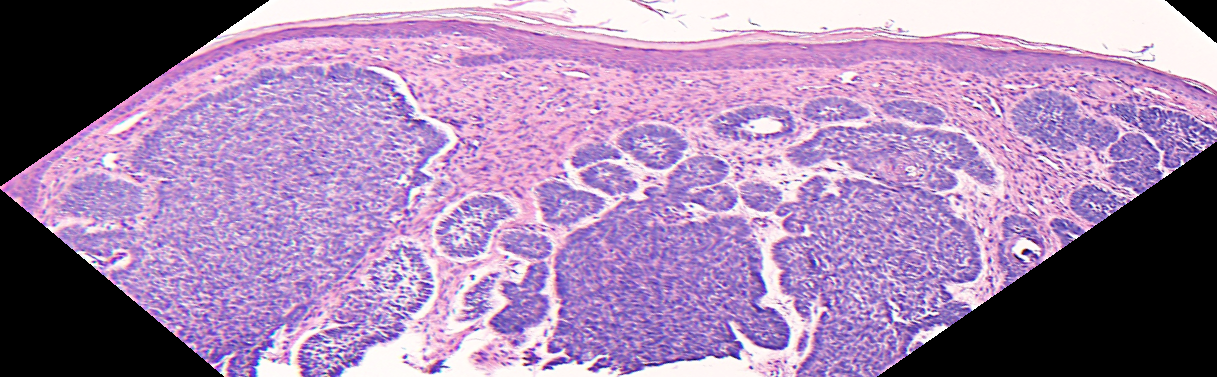

VA54: Left Superior Temple, Basal Cell Carcinoma, Nodular

- * denotes area of liquifactive necrosis with remnant necrotic cell debris